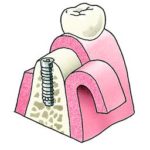

Een tandheelkundig implantaat is in wezen een titaniumschroef of -cilinder, tussen 4 mm en 16 mm lang, die wordt ingebracht in een voorbereide holte in de kaak en fungeert als een vervangende wortel voor de ontbrekende tand of kies. Een speciale bevestiging, het abutment genaamd, wordt aan de bovenkant van het implantaat bevestigd en vormt de externe verbinding met de vervangende tand (kroon). Er zijn ook implantaten uit één stuk waarbij het abutment en het implantaat deel uitmaken van één stuk.

- Plaatsen van kronen of bruggen: Uw tandarts zal de kronen cementeren of schroeven op de abutments over de implantaten, controleren of ze goed passen en er goed uitzien, en controleren of uw boven- en ondertanden comfortabel samenwerken als u bijt. Meestal moet u terugkomen voor verschillende beoordelingsafspraken om er zeker van te zijn dat de implantaten stabiel zijn en goed functioneren, en dat u helemaal tevreden bent met het eindresultaat.